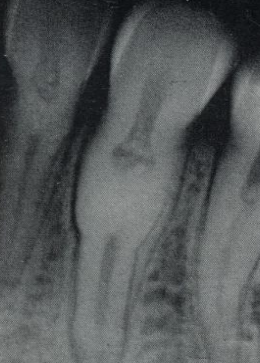

deep surface enamel invagination of the crown or root “tooth within tooth”; can be coronal (most frequent) or radicular

dens invaginatus “dens in dente”

“dens in dente” type I

invagination is confined to the crown

“dens in dente” type II

invagination extends below the CEJ

“dens in dente” type III

invagination may extend through the root